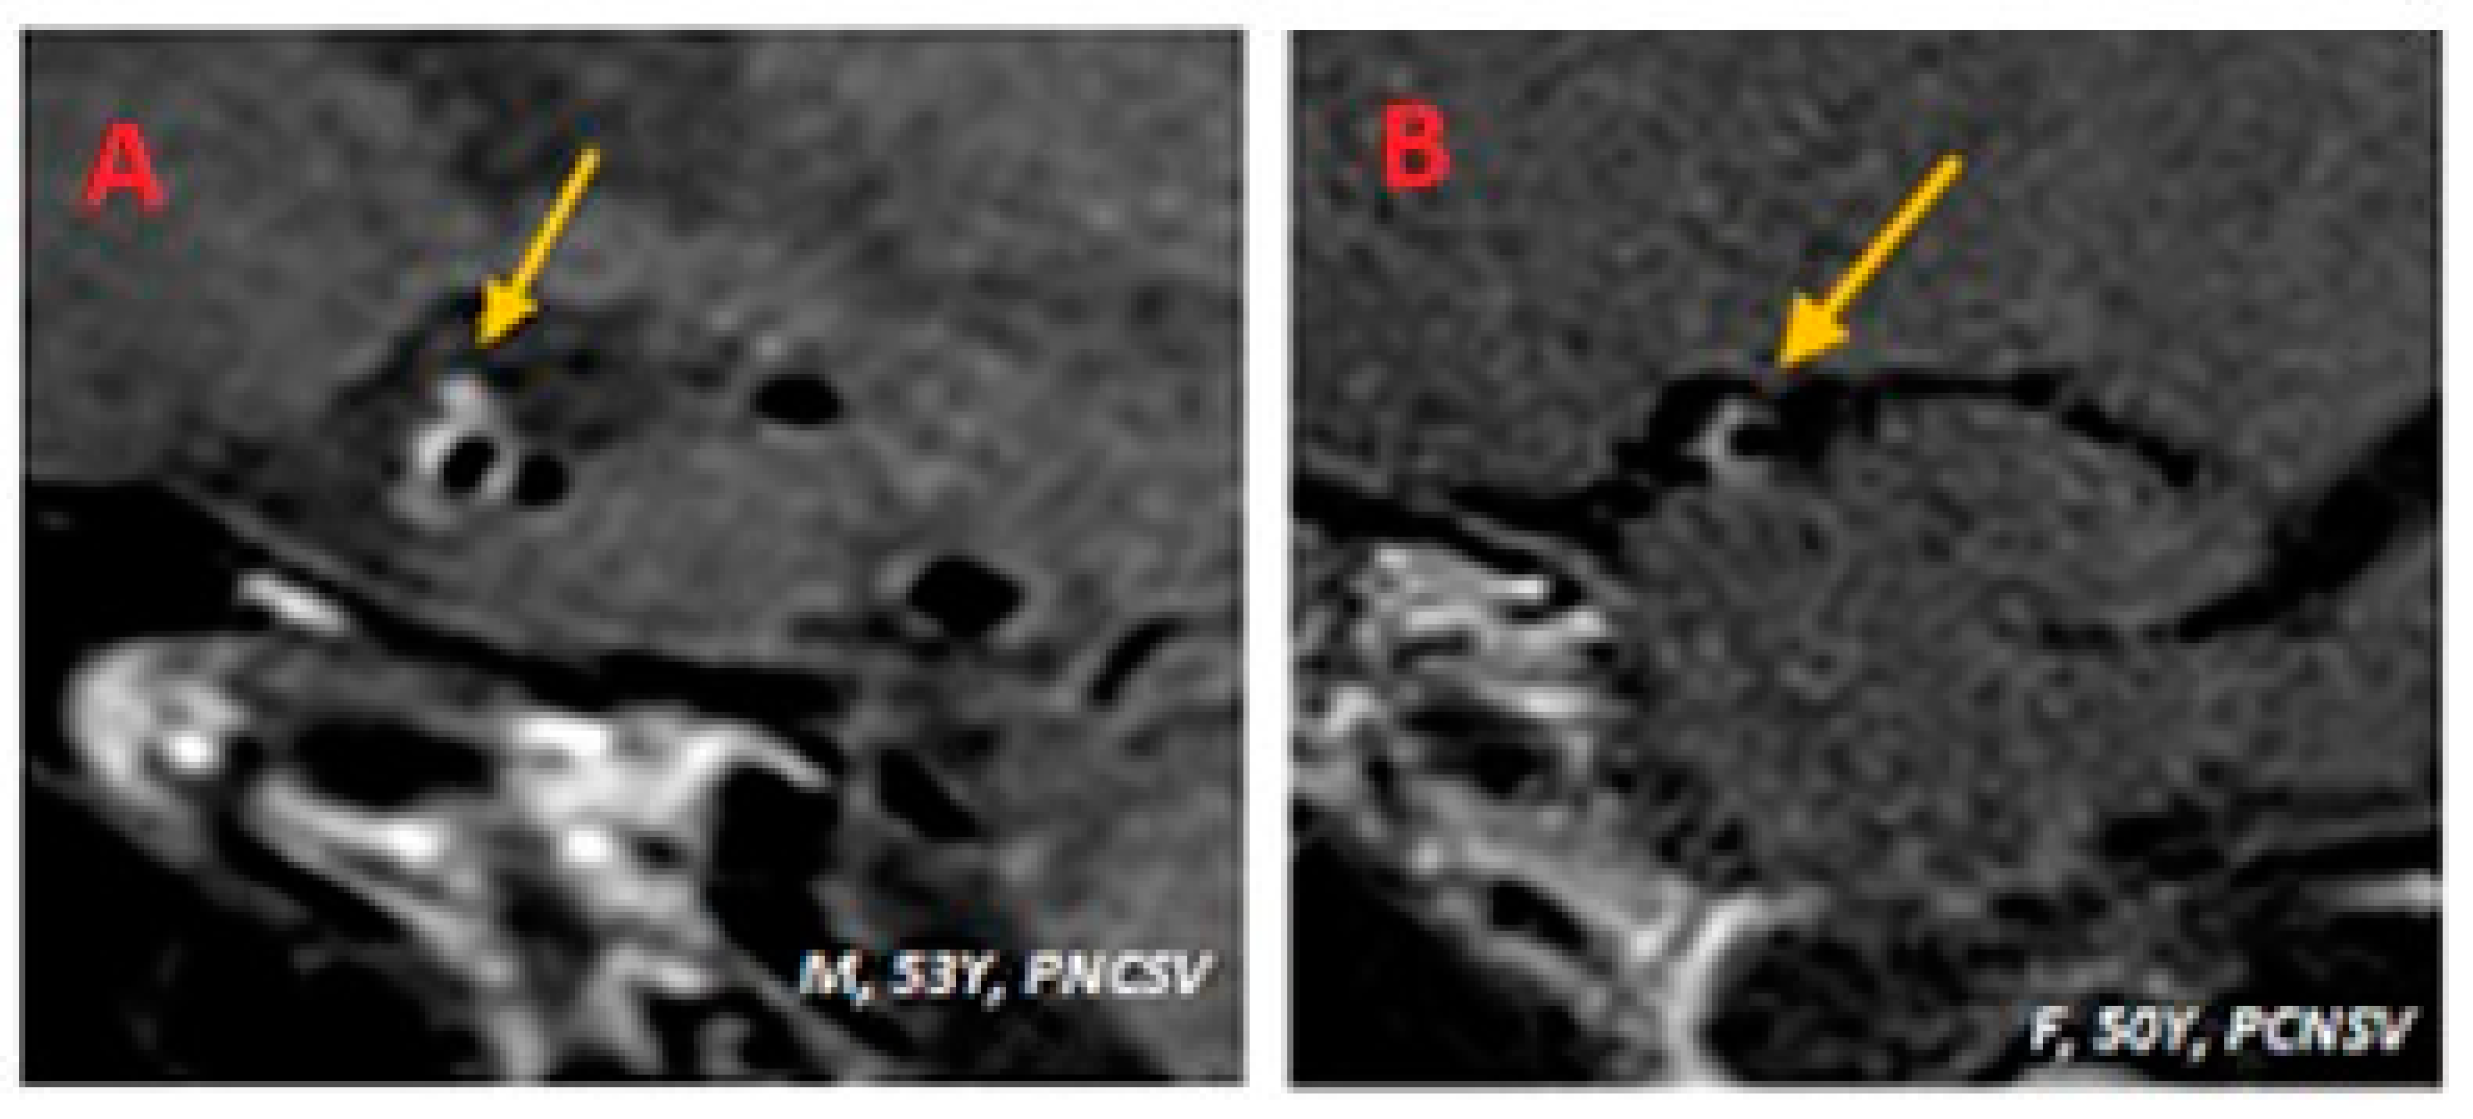

| 53Y M | Episode suggestive of stroke | Non-significative positive | Positive ENA+, anti-SSA RO52 | Negative | Negative | PCNSV |

| 53Y, M | 1 | Present | Present | Fight corona radiata | ICA | ACOP | Present | Supratentorial |